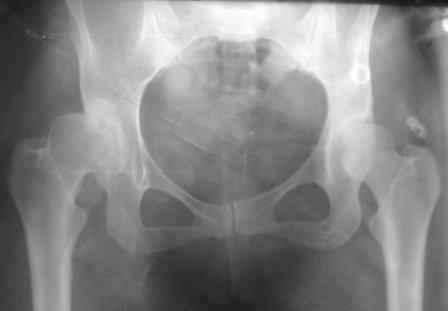

Представляю Р-снимки: обзорная, с отведением и с приведением.

Глубокоуважаемый Абдурашид. Здесь нет снимка с отведением. Если Вы сами сходили в рентгенкабинет и лично отвели пораженную конечность максимально возможно, а также дали максимально возможную внутреннюю ротацию-это одно!!!! Значит у пациентки тяжелейшая приводящая контрактура тазобедренного сустава!! И необходимо разобраться-миогенная или артрогенная? Если же Вы просто назначили указанный снимок и доверили произвести укладку рентгентехнику-это другое!!! Одному богу известно, что она делала, ведь на р-снимке отведения нет!

Все предыдущие корреспонденты предлагают вам достаточно простую вещь-смоделировать предлагаемую Вами операцию (т.е. дать отведение и внутреннюю ротацию) и посмотреть, как изменятся соотношения в суставе. Не обижайтесь, но судя по представлению клинического случая угловые величины, характеризующие пространственные соотношения в тазобедренном суставе, ваши рентгенологи не считают.

Уважаемый Игорь Владимирович. диссертации М М Камоска, и В Е Баскова я нашел, но почему-то не могу открывать, и еще в данном случае имеется дисплазия т/б за счет недоразвития крыши в/впадины да и всей подвздошной кости, маргинального вывиха или латеропозиции головки вследствие лечебных ощибок нет, головка стоит на месте. Р-граммы сделал сам, но почему-то у больной отведение и внутренная ротация стали очень болезненной, и сухожилия приводящих мышц сильно натягивается.(контрактура артро-миогенная).

Глубокоуважаемый Игорь Владимирович! Признаюсь допустил ошибку, из-за напряженности работы и нехватки времени, когда повторно внимательно посмотрел все понял и не успел исправить ошибку до Вашего поста, конечно скошенность крыши в пределах 40гр,часть головки кнаружи линии Омбредана-Перкинса , облитерация дна вертлужной впадины и т.д.-это ДМВБ.